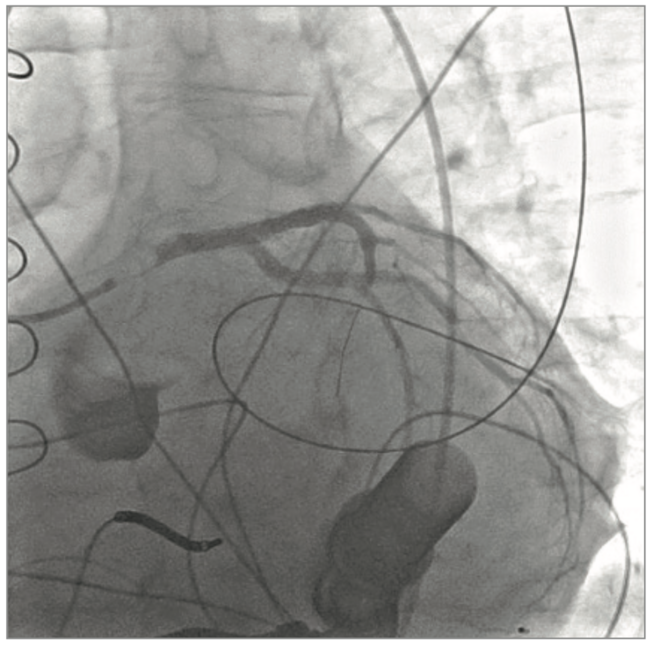

A 60 year-old gentleman with longstanding stage D non-ischemic cardiomyopathy and left ventricular ejection fraction of 10% underwent Heartmate II left ventricular assist device (LVAD) implantation (Abbott) after presenting with acutely decompensated heart failure. He was heterozygous for Factor V Leiden thrombophilia, with prior deep vein thrombosis and pulmonary embolism. Five days following LVAD implantation, he developed incessant ventricular fibrillation (VF) with evidence of ST elevations in anterior precordial leads. Flows on LVAD were reduced during the VF, but he remained relatively hemodynamically stable. Per standard LVAD protocol, he was on antiplatelet therapy with 81mg of aspirin daily, and IV unfractionated heparin while awaiting to achieve a therapeutic INR. INR at the time of STEMI was 1.17, but aPTT was therapeutic at 57.9 seconds on weight-based IV unfractionated heparin. The catheterization lab was emergently activated.